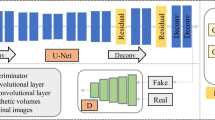

Organ segmentation from existing imaging is vital to the medical image analysis and disease diagnosis. However, the boundary shapes and area sizes of the target region tend to be diverse and flexible. And the frequent applications of pooling operations in traditional segmentor result in the loss of spatial information which is advantageous to segmentation. All these issues pose challenges and difficulties for accurate organ segmentation from medical imaging, particularly for organs with small volumes and variable shapes such as the pancreas. To offset aforesaid information loss, we propose a deep convolutional neural network (DCNN) named multi-scale selection and multi-channel fusion segmentation model (MSC-DUnet) for pancreas segmentation. This proposed model contains three stages to collect detailed cues for accurate segmentation: (1) increasing the consistency between the distributions of the output probability maps from the segmentor and the original samples by involving the adversarial mechanism that can capture spatial distributions, (2) gathering global spatial features from several receptive fields via multi-scale field selection (MSFS), and (3) integrating multi-level features located in varying network positions through the multi-channel fusion module (MCFM). Experimental results on the NIH Pancreas-CT dataset show that our proposed MSC-DUnet obtains superior performance to the baseline network by achieving an improvement of 5.1% in index dice similarity coefficient (DSC), which adequately indicates that MSC-DUnet has great potential for pancreas segmentation.